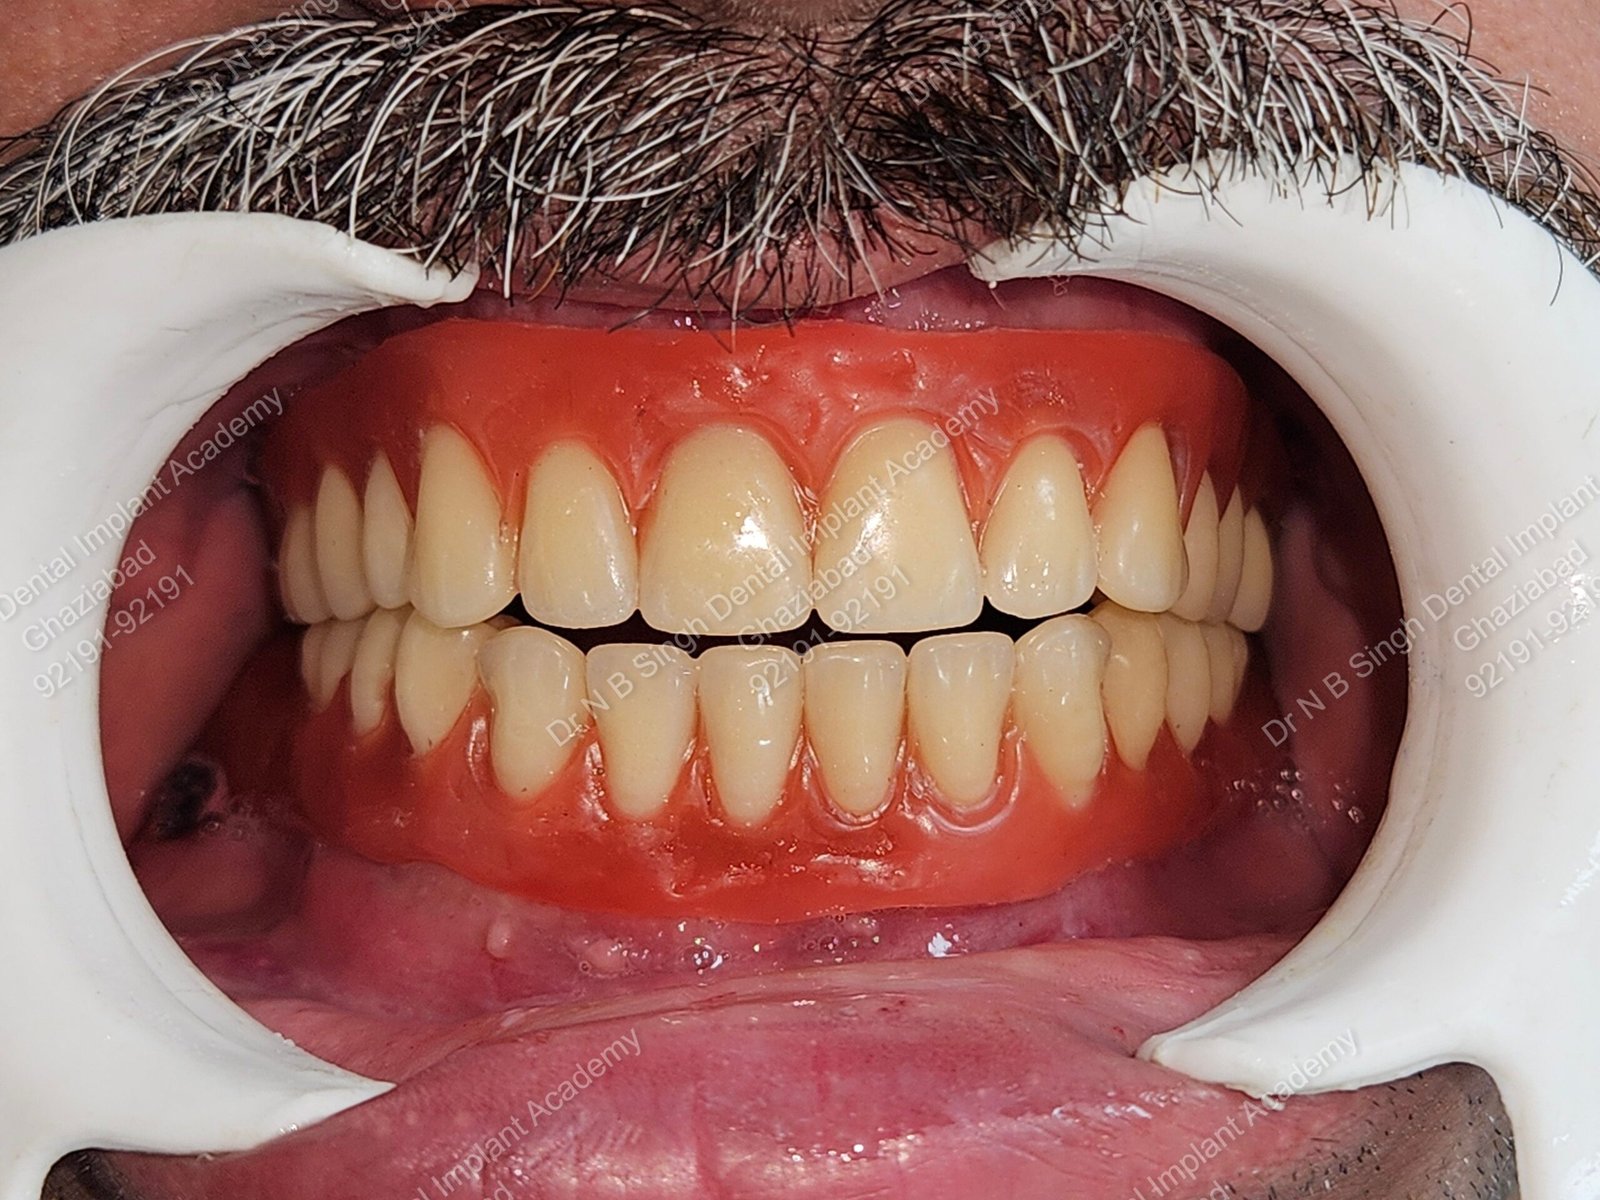

1006 Basal implant full mouth-DEEPAK